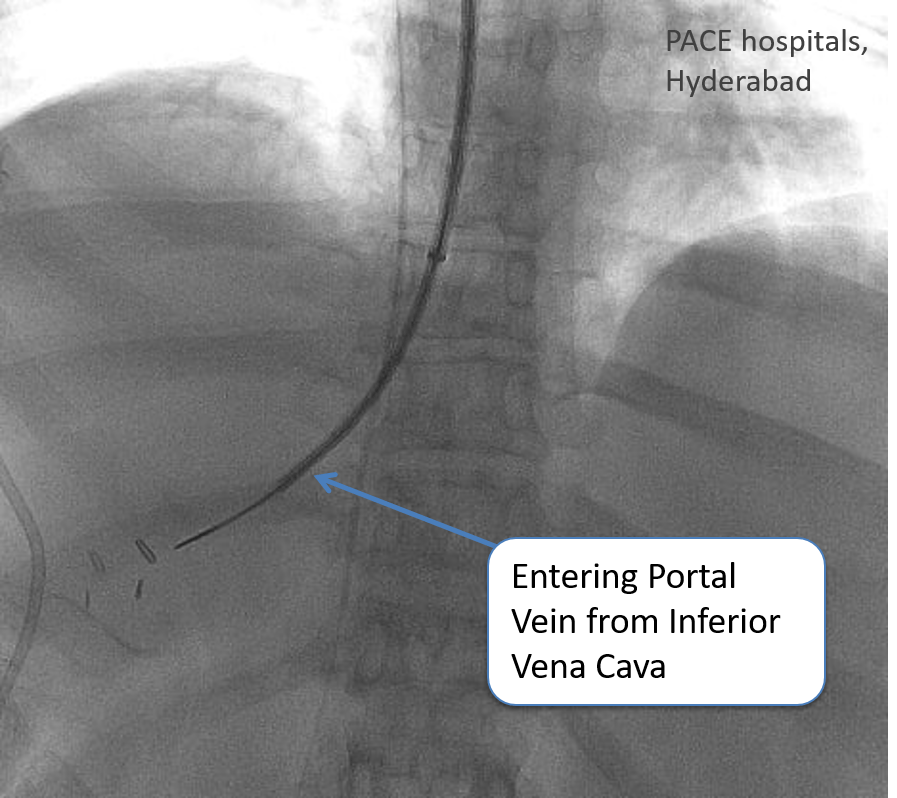

So to treat this condition, we did an interventional radiology procedure called Direct Intrahepatic Portosystemic Shunt (DIPS).

DIPS or TIPS (Transjugular Intrahepatic Portosystemic Shunt) is considered as one of the most difficult interventional radiology procedure. It is performed in only a handful of centers in India.

If Budd-Chiari syndrome is detected early, medicines to break the clots can be used for treatment. But most of the time this is detected late. These patients can be treated with interventional radiology techniques. These techniques include opening the blocked vein using balloon (angioplasty) or stent. In patients with veins not amenable for opening, TIPS procedure can be done. In this procedure, a new outflow to liver blood is created by bridging the inflow vessel (portal vein) and the inferior vena cava.

What is the DIPS procedure and when is it used?

The Direct Intrahepatic Portosystemic Shunt (DIPS) procedure creates an alternate pathway for blood to bypass blocked hepatic veins. It is especially useful when conventional shunt procedures are not feasible.

How does DIPS differ from other shunt procedures?

Unlike traditional shunts, DIPS procedure directly connects the portal vein to the inferior vena cava. This approach is beneficial in patients with complete hepatic vein obstruction.